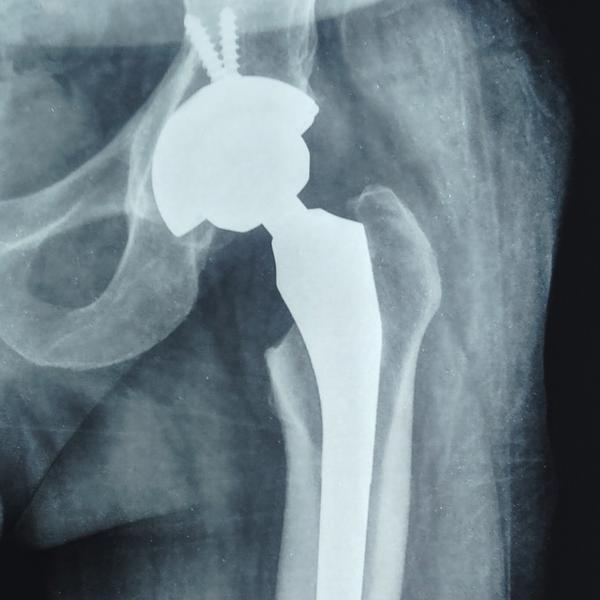

Successful Hip Replacement surgery in Greater Noida/ Noida

SUCCESSFUL HIP REPLACEMENT SURGERY for Hip fracture /AVN HIP joint